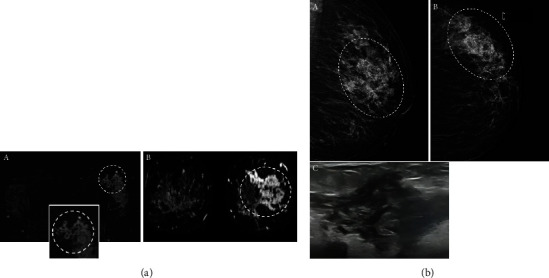

Dynamic contrast-enhanced magnetic resonance imaging (DCE-MRI) is a highly sensitive breast imaging modality in detecting breast carcinoma. Nonmass enhancement (NME) is uniquely seen on MRI of the breast. The correlation between NME features and pathologic results has not been extensively explored. Our goal was to evaluate the characteristics of probably benign and suspicious NME lesions in MRI and determine which features are more associated with malignancy. We performed a retrospective research after approval by the hospital ethics committee on women who underwent breast MRI from March 2017 to March 2020 and identified 63 lesions of all 400 NME that were categorized as probably benign or suspicious according to the BI-RADS classification (version 2013). MRI features of NME findings including the location, size, distribution and enhancement pattern, kinetic curve, diffusion restriction, and also pathology result or 6-12-month follow-up MRI were evaluated and analyzed in each group (probably benign or suspicious NME). Vacuum-guided biopsies (VAB) were performed under mammographic or sonographic guidance and confirmed with MRI by visualization of the inserted clips. Segmental distribution and clustered ring internal enhancement were significantly associated with malignancy (p value<0.05), while linear distribution or homogeneous enhancement patterns were associated with benignity (p value <0.05). Additionally, the plateau and washout types in the dynamic curve were only seen in malignant lesions (p value <0.05). The presence of DWI restriction in NME lesions was also found to be a statistically important factor. Understanding the imaging findings of malignant NME is helpful to determine when biopsy is indicated. The correlation between NME features and pathologic results is critical in making appropriate management.

Abstract Image